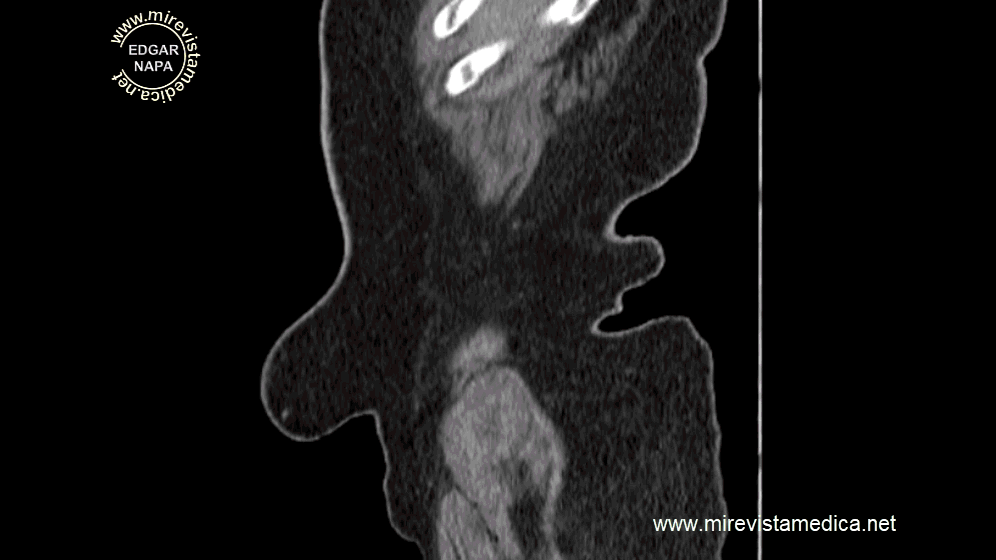

Las hernias de la línea media se producen por la salida de contenido epiploico y / o intestinal a través de un defecto en la línea media anterior.

Las hernias se pueden producer al reposo o por incremento de la presion intrabdominal (maniobra de valsalva

Cuando las hernias no pueden reducirse al acabar la maniobra de valsalva, se denominan no reductible.

En estos casos se debe valorar otros signos como las colecciones dentro del saco herniario o perdida del flujo del asa intestinal herniada, dolor intenso que no cesa; Su presencia la denominaría como hernia incarcerada.